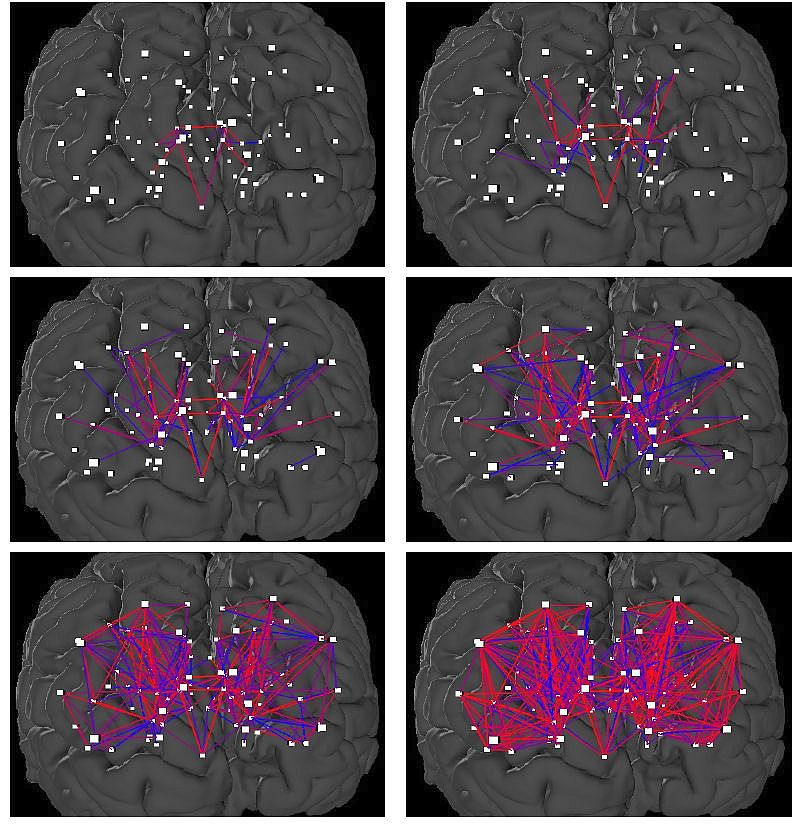

A biológiában rendkívül ritkán fordul elő az, hogy ugyanazon a csúcshalmazon sok különböző gráfot vizsgálnak. Az agygráfoknál azonban ez a tipikus helyzet: a csúcsok az agy szürkeállományának anatómiailag azonosított 1–1,5 cm2-es területeinek felelnek meg, és két csúcs éllel van összekötve, ha egy diffúziós MRI-alapú eljárással közvetlen, idegrostokból álló összeköttetést fedeznek fel a csúcsoknak megfelelő, szürkeállománybeli területek között. A webszerver segítségével lehet megjelentetni és ábrázolni a kisebb, illetve a nagyobb gyakorisággal megjelenő agyi kapcsolatokat, azaz az agygráf ritkábban és gyakrabban előforduló éleit.

Az ELTE-s kutatócsoport doktori hallgatója, Kerepesi Csaba a webszerver publikálása után, rendkívül meglepő észrevételt tett. Azok az élek, amelyek a vizsgált alanyok 100%-ában jelen vannak, nyilvánvalóan kevesebben vannak, mint azok az élek, amelyek csak az alanyok legalább 75%-ban vannak jelen, és ezek kevesebben vannak, mint azok, amelyek legalább 50%-ban vagy mondjuk legalább 25%-ban vannak jelen. Tehát ha tekintjük azokat az agyi kapcsolatokat, amelyek az alanyok legalább x százalékában vannak jelen, és az x-et csökkentjük 100-tól 1-ig, akkor egyre több kapcsolatot kapunk, egyre több él lesz a gráfunkban.

A megdöbbentő észrevétel az, hogy az élek nem véletlenül, szétszórva jelennek meg az x paraméter csökkentésével, hanem egy növekedő fához hasonlóan, többnyire a már meglevő élekhez csatlakozva. (Ezt mutatja a mellékelt ábra is, a jelenségről itt megtekinthető egy animáció. Az ELTE-s webszerveren bárki saját maga is megtapasztalhatja a jelenséget, ha a „Show options” választás után a „Minimum edge confidence” csúszkát jobbról balra tolja el, és közben figyeli a megjelenő éleket.)